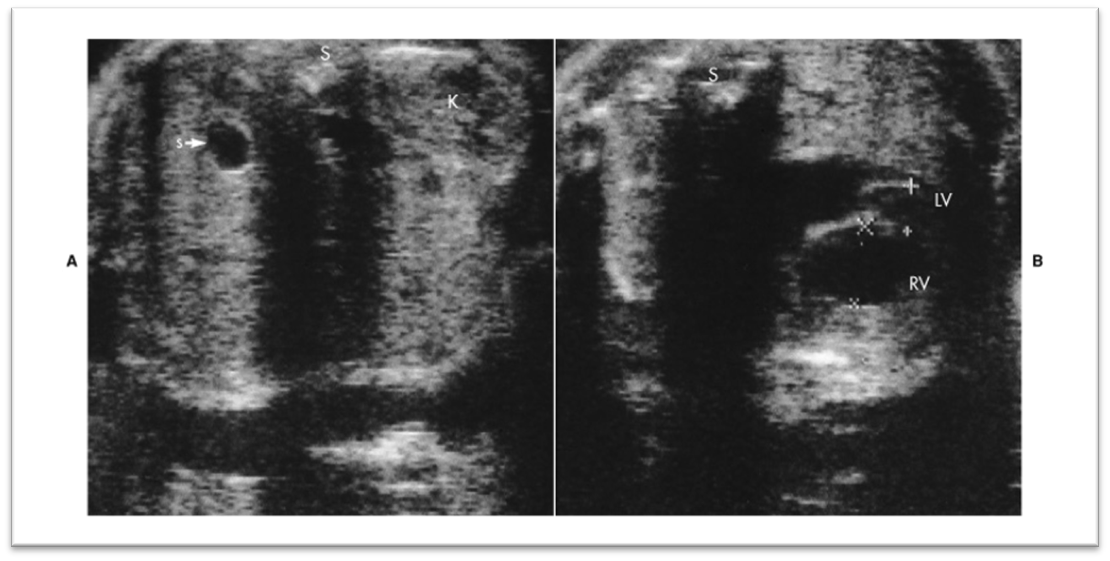

What is this image showing?

Partial situs- stomach on right and hypoplastic left heart